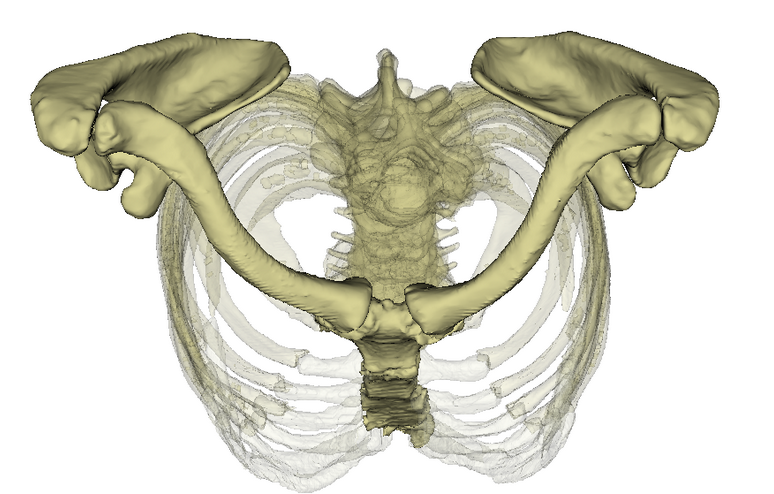

Die Haltemuskeln an den Querfortsätzen der Wirbelkörper stabilisieren die Wirbelsäule, machen die Feinabstimmung und führen kleine Bewegungen (Rotation, Seitneigung) aus. Die Hals- und obere Brustwirbelsäule ist das Punctum fixum bei Bewegungen im Schultergürtel und dem Schultergelenk. Im Gegensatz zum Beckengürtel, der knöchern geschlossen ist und somit für Stabilität in der unteren Körperhälfte sorgt, ist der Schultergürtel zwischen Schulterblatt und Hals-/Brustwirbelsäule offen und wird muskulär geschlossen, was eine Drehung des Schulterblattes ermöglicht und somit die Bewegungsfreiheit im Schultergelenk deutlich erhöht. Bei Überkopfarbeiten oder manuelle Arbeiten ohne aufgelegte Arme muss diese Muskulatur die Stabilität am Körperstamm leisten und ermüdet bei längerem Gebrauch (> 2–3 Stunden). Übermüdung ist immer mit Verkürzung (Schutzmechanismus der Muskeln) und Verspannung verbunden.

Bandscheiben sind die Druckpolster zwischen den Wirbelkörpern und ermöglichen — ähnlich wie bei einer Fahrradkette — eine Bewegung der sonst knöchernen Wirbelsäule vorwärts, rückwärts und seitwärts sowie eine Rotation. Bandscheiben haben keine Blutgefäße und ernähren sich durch Diffusion mit Nährstoffen aus der umgebenden Flüssigkeit. Ermöglicht wird das durch Druck und Sog. Wenn nun durch die Verspannung der Muskulatur ein Dauerdruck auf den Bandscheiben lastet kommt es zu Ernährungsstörungen — insbesondere des Faserringes, der den gallertartigen Kern ummantelt. Der Faserring reißt langsam ein, der gallertartige Kern wölbt sich an dieser Stelle vor und man spricht von einer/-m Bandscheibenprotrusion/-prolaps. Reißt er komplett durch kommt es zu einem Massenvorfall, der immer eine Akutintervention erfordert, da er auf das Rückenmark drückt. Bei Vorwölbung im Bereich des seitlichen Wirbelloches, wo der Rückenmarksnerv austritt kann es zu einer Kompression kommen. Bedingt durch die Lage der einzelnen Nervenfasern kommt es zunächst zu Schmerz, danach zu Gefühlsstörungen im Bereich des versorgten Gebietes (Dermatom) und letztendlich dann auch zu Muskellähmung, die immer eine sofortige chirurgische Intervention erforderlich machen.